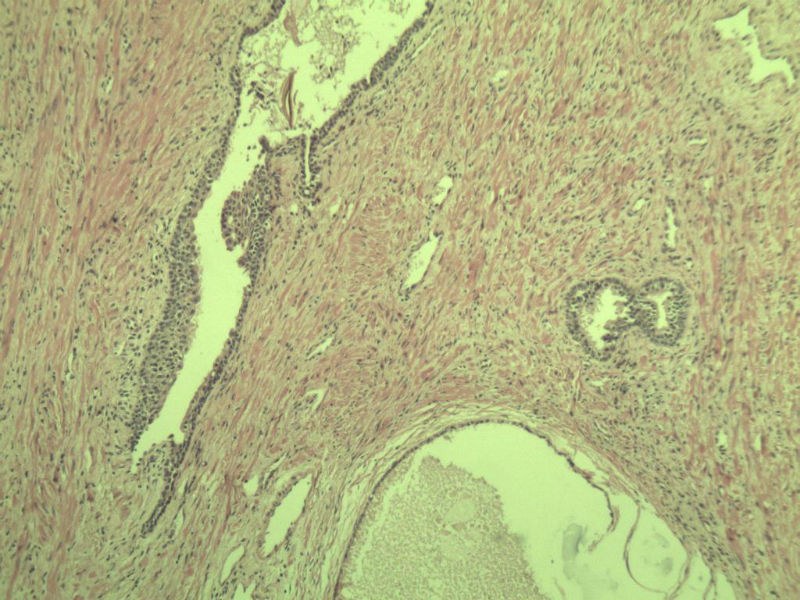

男 75岁 因排尿困难半年行前列腺切除术,体积 4 × 3 × 2.5 cm3,切面灰白,实性,质韧。请各位老师看看 有问题没? 谢谢了!

良性前列腺增生伴尿路上皮化生

前列腺增生症伴鳞化

前列腺增生伴尿路上皮鳞化及Brown巢形成,未见恶性。